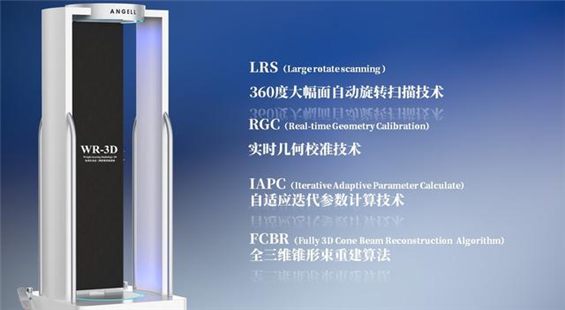

安健科技基于數字化X線攝影技術創新的WR-3D負重位多角度三維掃描系統

安健科技WR-3D負重位動態三維攝影技術